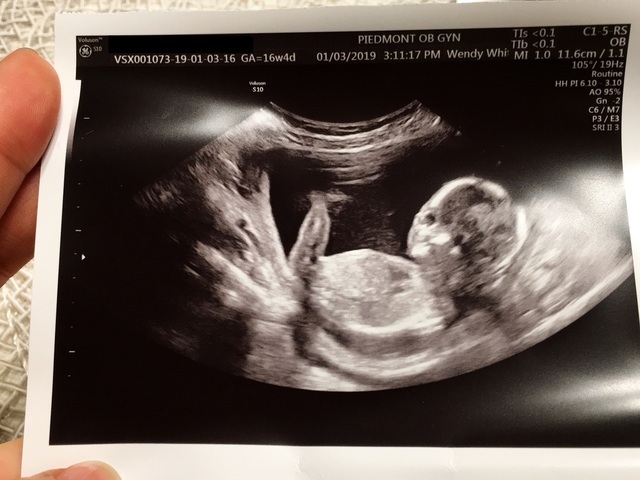

19週3日(19w3d・男の子)|パタリロ(’ω’) さん(29歳)

エコー写真撮影時のエピソード:

前日に風邪をひいて熱を出してしまい、お腹の赤ちゃんが心配でしたがエコーで先生に元気ときいてひとまず一安心。

そしてこの日は性別がわかるかもとゆう大切なエコー撮影の日。夫と一緒にドキドキしながらエコーの結果を待ちます!

先生からは『はっきりとわかりましたよ!男の子です』と言われ大感激!まだ15センチくらいなのにちゃんと男の子なんだなぁと私はなんだか不思議な感覚。

夫は『2人の予想通り!嬉しい〜』とニコニコ♪今でもあの嬉しい瞬間は大切な思い出!このエコー写真には性別のわかる部分は写ってないけれど2人ともこの写真が携帯の待ち受け画面。宝物です!